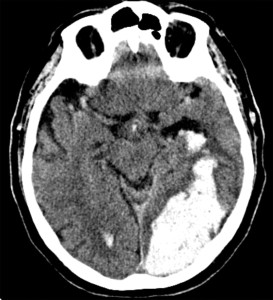

The study is a pooled analysis from the Oxford Vascular Study (OXVASC) and the Lothian Audit of the Treatment of Cerebral Haemorrhage (LATCH). It analyzed 674 first-time ICH patients over 1553 person-years. The cohort’s mean age was 74.7, 47% were male, and 51% were on antithrombotics before their ICH. Additionally, 22% had atrial fibrillation, and 47% had lobar ICH while the rest had non-lobar ICH.

The recurrent ICH rate was 3.2 per 100 person-years based on 46 events in the cohort. The ischemic stroke rate was 1.7 per 100 person-years from 25 events, and the rate for any serious vascular event was 7.9 per 100 person-years from 118 events. Lobar ICH had a higher risk of recurrent hemorrhage with a hazard ratio (HR) of 3.2 (95% CI 1.6-6.3; p=0.0010). Ischemic stroke risk was not location-dependent with an HR of 1.1 (95% CI 0.5-2.8; p=0.76). Atrial fibrillation at the time of the initial ICH increased ischemic stroke risk significantly (HR 8.2, 95% CI 3.3-20.3; p<0.0001).

The study accentuates the importance of two critical risk-stratification parameters for post-ICH management: the anatomical location of the hemorrhage and the presence of comorbid atrial fibrillation. The anatomical location, specifically whether it’s lobar or non-lobar, can be a predictive factor for the likelihood of recurrent hemorrhages. Conversely, atrial fibrillation is a crucial determinant for assessing the heightened risk of ischemic stroke. These risk stratification elements not only lend support to the findings of the RESTART trial but also underscore the urgency for specialized clinical trials that aim at targeted interventions for high-risk subgroups.

Check out some relevant images from our website below: